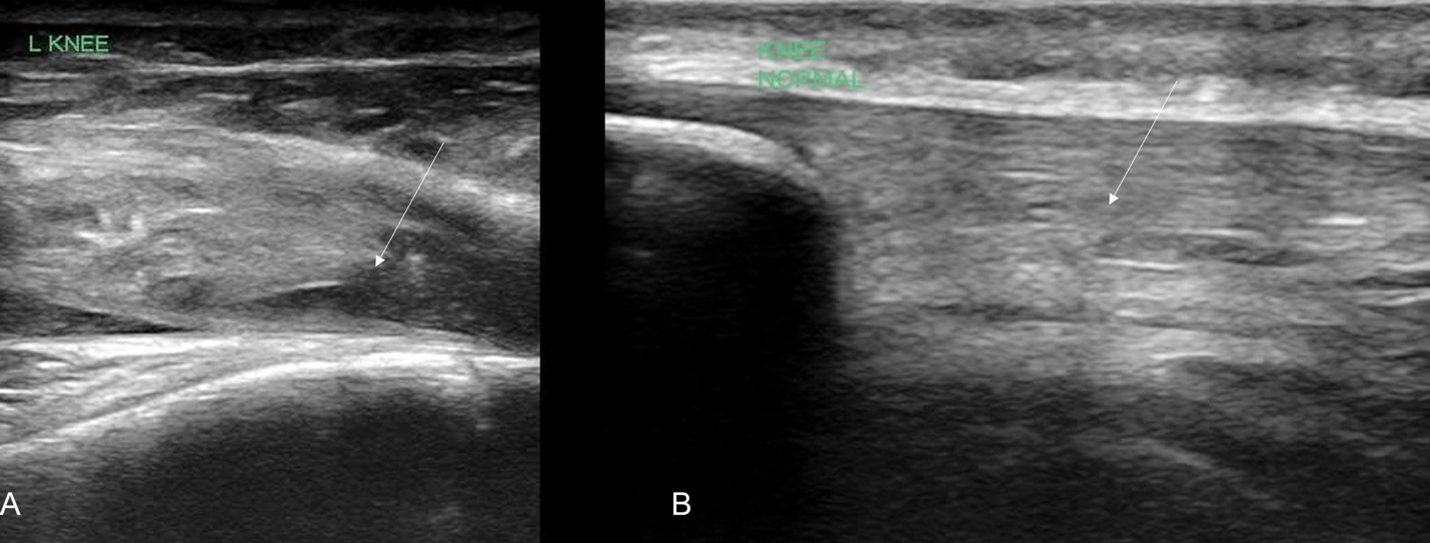

POCUS of the left knee was performed, which was concerning for a patellar tendon rupture and a joint effusion. (Figure 1 and Video 1) In addition, there was posterior acoustic shadowing obscuring part of the patellar tendon concerning for an avulsed bony fragment. (Figure 2) X-rays were performed, which confirmed the suspected diagnosis of a left tibial tubercle avulsion. (Figure 3) The patient was ultimately taken to the operating room for an Open Reduction and Internal Fixation (ORIF) by Orthopedic Surgery and discharged home the following day in a knee brace.

Figure 1. Ruptured patellar tendon (arrow) with joint effusion (*) seen in longitudinal view

In our case report, we successfully identified key features suggestive of tibial tubercle fractures: disruption of the patellar tendon, posterior acoustic shadowing of a bone fragment, and a large joint effusion. To perform knee ultrasound, the linear probe should be used and placed inferior to the patella in sagittal plane. The patellar tendon should be visualized in two planes, fanning through it completely (Video 1), and compared to the contralateral normal knee. (Figure 4) Abnormal findings suggestive of epiphyseal fractures include disruption of the tendon, an increased hypoechoic space adjacent to or posterior to the tendon (suggestive of either hemarthrosis or a hematoma), or a hypoechoic zone (ie, posterior acoustic shadowing due to an avulsed bony fragment).3,4

Figure 4: A) Ruptured tendon (arrow) in comparison against (B) contralateral knee indicating the normal continuous tendon fibers (arrow)